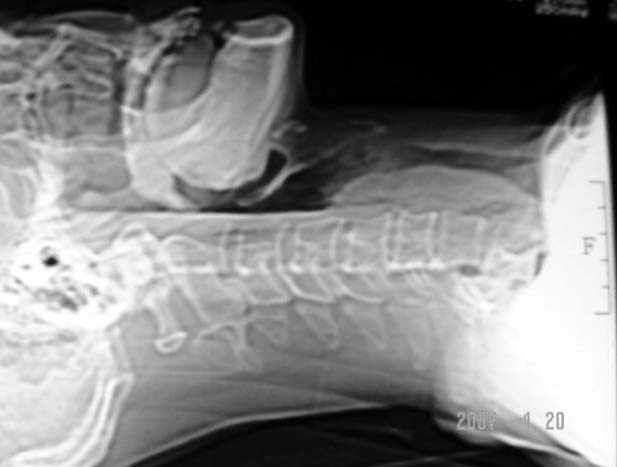

以下是引用dyqct在2007-4-20 16:19:00的发言:[br]考虑:1、左侧梨状窝区破裂伴左颈深、浅部气肿。[br] 2、右侧甲状腺区血肿(请追问病史是否伤及右颈部)。[br] 3、建议病情稳定后增强扫描除外右侧甲状腺腺瘤。